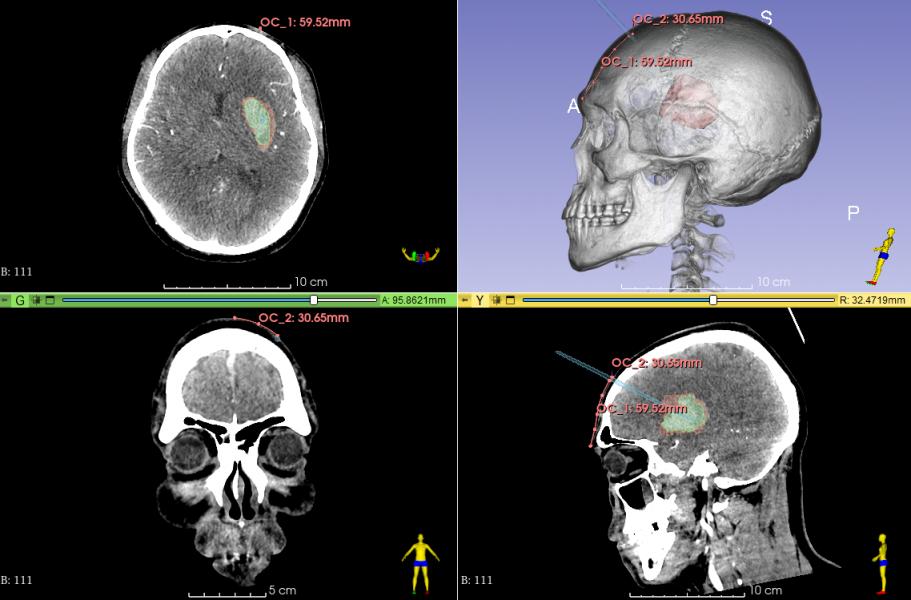

数字化定位穿刺部位

发际内,中线旁开3.0cm

有效避开额部血管